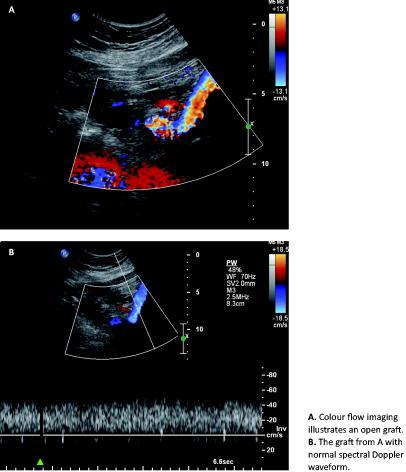

The mean age of the six women and four men was 42.5 years (range 26-61 years); no comorbidity was reported. Routine follow-up included a clinical examination as well as colour duplex scan of the relevant segment with a view to evaluating venous patency at three months postoperatively and once a year. The median follow-up period was 16 months (range 12-157 months). The number of patients was too small for statistical analysis.

The venous patency rate was 90% after supplementary treatment. The colour duplex scan showed that nine patients had open PTFE grafts. However, one patient had a PTFE graft stenosis, but flow in the iliac externa vein, which corresponded to the genuine system via collaterals. This was the only case in which the PTFE graft was inserted end-to-side. One stenosis was identified seven months postoperatively. The patient was treated with a stent. At the latest follow-up (range from 12 months to 13 years), four patients had injury-related complications such as subjective symptoms of tiredness and heaviness, three of whom had tendencies towards limb oedema and two of whom had segmental reflux: one in the popliteal vein and one in the femoral vein. The morbidity rate was 40%. No patients died during follow-up.

We had a 30-day patency rate of 70% and at the latest follow-up, the venous patency rate was 90% after supplementary treatment. But even though the PTFE grafts were open in nine out of ten cases, four patients still had subjective symptoms, three of whom had tendencies towards oedema. The oedema in these patients might be caused by the segmental reflux shown by colour duplex in two cases or by injury and manipulation itself at the primary operation, which may have resulted in lymphatic damage.